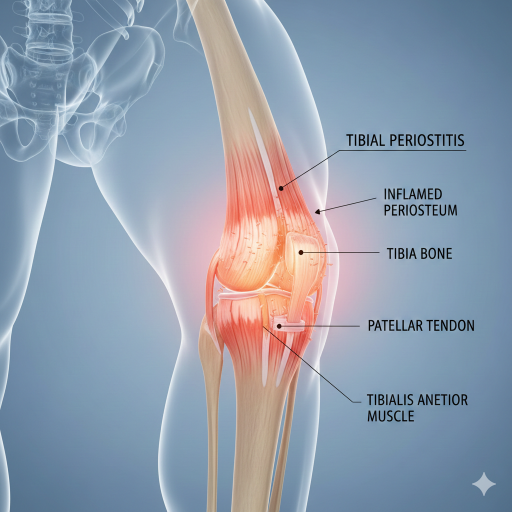

Periostite Tibial (Síndrome da Stress Medial da Tíbia – SSMT)

A Periostite Tibial é a inflamação do periósteo (a membrana fina que cobre o osso) e/ou dos músculos e tendões que se inserem ao longo da borda medial (interna) da tíbia. É uma lesão de sobrecarga comum em corredores e atletas que praticam desportos de alto impacto.